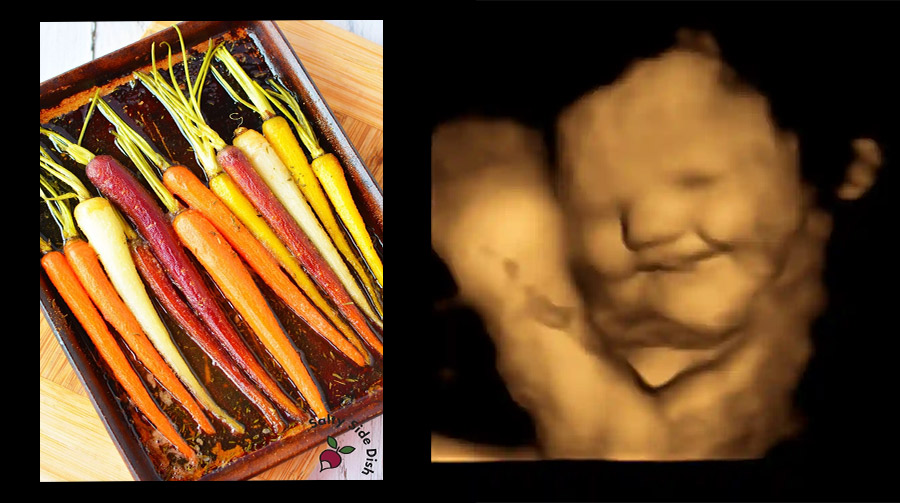

NOVO ISTRAŽIVANJE Prvi put su snimljene reakcije još nerođene djece na hranu. Bebe osjećaju okuse od 24. tjedna trudnoće

Snimanja su napravljena na Sveučilištu Durham pod vodstvom profesorice Nadje Reissland. Rezultati su objavljeni u časopisu  Psychological Science. Znanstvenici su primjetili da se aromatski spojevi koji nastaju prehranom majke mogu pronaći u plodnoj vodi. Slijedom toga, tek nastali okusni pupoljci bebe već u 14. tjednu trudnoće mogu registrirati okuse, a od 24. tjedna aromatske molekule.

Znanstvenike je nadalje zanimalo mogu li bebe prije rođenja osjetiti razliku među okusima. Napravili su ultrazvučne snimke s gotovo 70 trudnica u dobi od 18 do 40 godina na sjeveroistoku Engleske. Trudnice su podijelili u dvije grupe. Jedna je grupa uzela kapsule s prahom dehidriranog kelja 20 minuta prije ultrazvuka, a druga prah od mrkve. Pregledali su i arhivske snimke 30 žena kojima nisu dane nikakve kapsule. Sve su zamoljene da se suzdrže od jela i pića  sat vremena prije snimanja. Zatim su ponovno analizirali sliku po sliku bilježeći različite pokrete lica beba, uključujući kombinacije koje su podsjećale na smijanje ili plakanje. Ukupno,  ispitali su 180 snimaka 99 beba skeniranih u 32 tjedna, 36 tjedna ili u obje vremenske točke. Ustanovili su da su bebe dvaput češće radile grimase plača kad je majka konzumirala kapsulu kelja u usporedbi s kapsulom mrkve ili ništa. Međutim, kada je majka konzumirala kapsulu mrkve, fetusi su poprimili izraz lica sličan smijehu otprilike dva puta češće nego kada je majka progutala kapsulu kelja ili nije progutala kapsulu. Dr. Benoist Schaal, autor znanstvenog rada iz Centra za okus i ponašanje pri hranjenju na Sveučilištu u Burgundiji, rekao je za Guardian da je jasnoća rezultata iznenađujuća.

“Snimke ukazuju da je beba i prije nego majka dovrši obrok već svjesna ili može osjetiti što je majka pojela”, rekao je. Beyza Ustun, prva autorica istraživanja, rekla je da na sveučilištu sada žele istražiti reakciju beba na različite okuse neporedno nakon rođenja. “Zanima nas hoće li njihove reakcije na određene okuse kojima su bile izložene prije rođenja imati veze s reakcijama na te iste okuse nakon rođenja. Recimo, hoćemo li vidjeti manje negativnih reakcija na kelj kod beba koje su njegovu okusu bile izložene prije rođenja.” Autori smatraju da ova studija biti i doprinos u raspravi o prehrani trudnica.  “Iz drugih istraživanja znamo da ako se majka hrani raznovrsno beba je nakon rođenja manje izbirljiva u jelu.” Zaključci ovog istraživanja jesu na tragu prethodnih, uz neke tehničke ograde vezane uz metodologiju.  Dakle, ako se želite poštedjeti maratonskih pregovora i izmišljanja igara da biste dijete nagovorili da jede, počnite razmišljati na vrijeme.